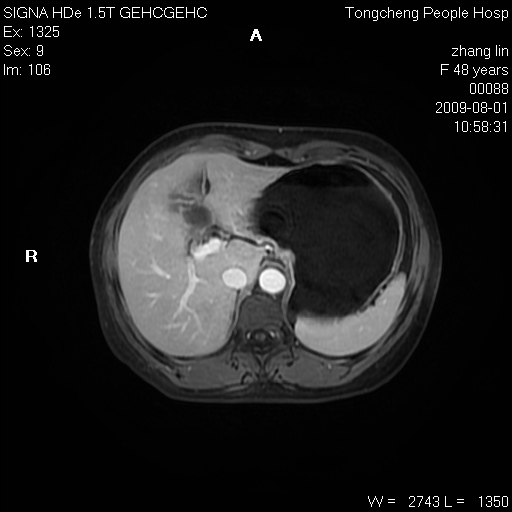

女,48岁。健康体检,彩超发现右肾占位性病变。平素健康。

临床诊断:右肾占位性病变,性质待定(囊肿?肿瘤?)。

上中腹部mr平扫+增强扫描,图像如下:

右肾上极见一类圆形病灶,t1wi呈等信号t2wi呈等高混杂信号,三期增强无强化,边界清---考虑囊肿出血。

肝囊肿